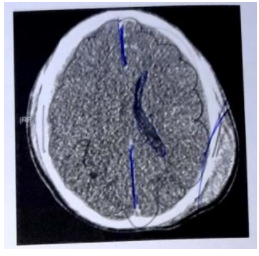

Paciente de 18 anos sofreu trauma de crânio por acidente com veículo automotor. Ao chegar à Emergência, foi intubado. Apresentava pupilas reativas de 5 mm e reflexos corneano e de tosse. Não havia abertura ocular à dor, e a postura era em extensão bilateral. A avaliação dos sinais vitais revelou pressão arterial de 139/83 mmHg, batimentos cardíacos de 101 bpm, frequência respiratória de 8 mpm e saturação de oxigênio de 98%. Exames laboratoriais indicaram hemoglobina de 9,7 g/dl e glicemia de 107 mg/dl. A tomografia computadorizada (TC) de encéfalo encontra-se reproduzida abaixo.

Qual a próxima medida a ser tomada?